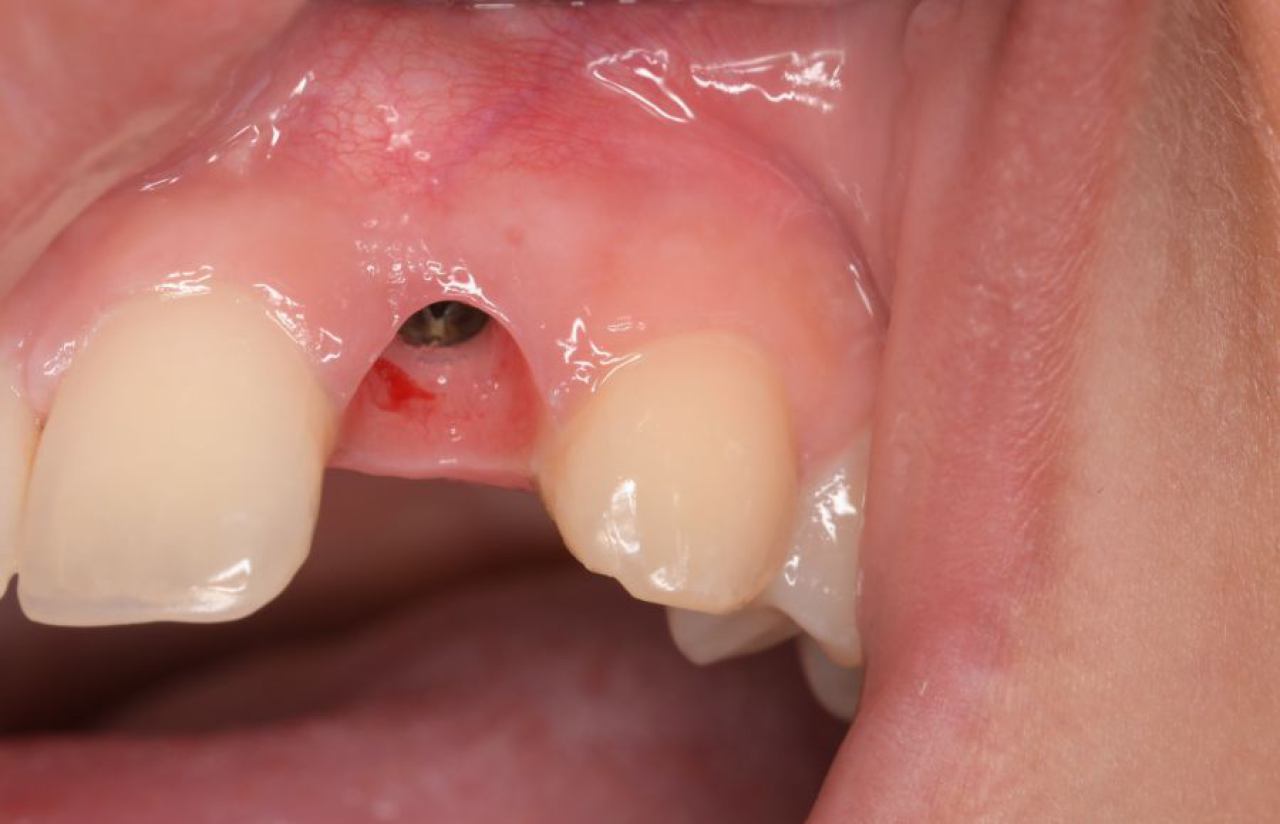

Implantologija - ugradnja dentalnih implantata

Dentalna implantologija je grana dentalne medicine koja objedinjuje znanje iz kirurgije, parodontologije i protetike i bavi se ugradnjom implantata u bezubu kost gornje ili donje čeljusti.

Marković Dental Clinic koristi najstariji, najistraživaniji i najkvalitetniji sustav dentalnih implantata Švedskog proizvođača Nobel Biocare.